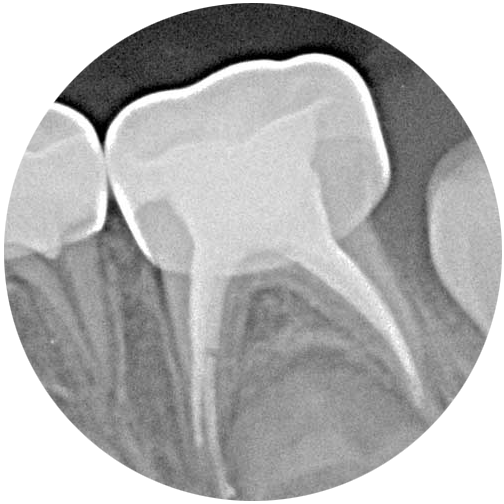

ROOT TREATMENT OF A MILK TOOTH

Due to the natural anatomical characteristics of a milk tooth - little enamel and a very large nerve - a root treatment of a milk tooth is required much more quickly than for a permanent tooth.

A so-called root amputation, in which only the upper part of the nerve is removed, is a very common procedure in children's treatment that can be carried out quickly and without problems. A complete root treatment is rarely necessary.